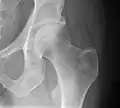

taki sam implant, jak na zdjęciu po lewej, umieszczony w ciele człowieka

staw biodrowy